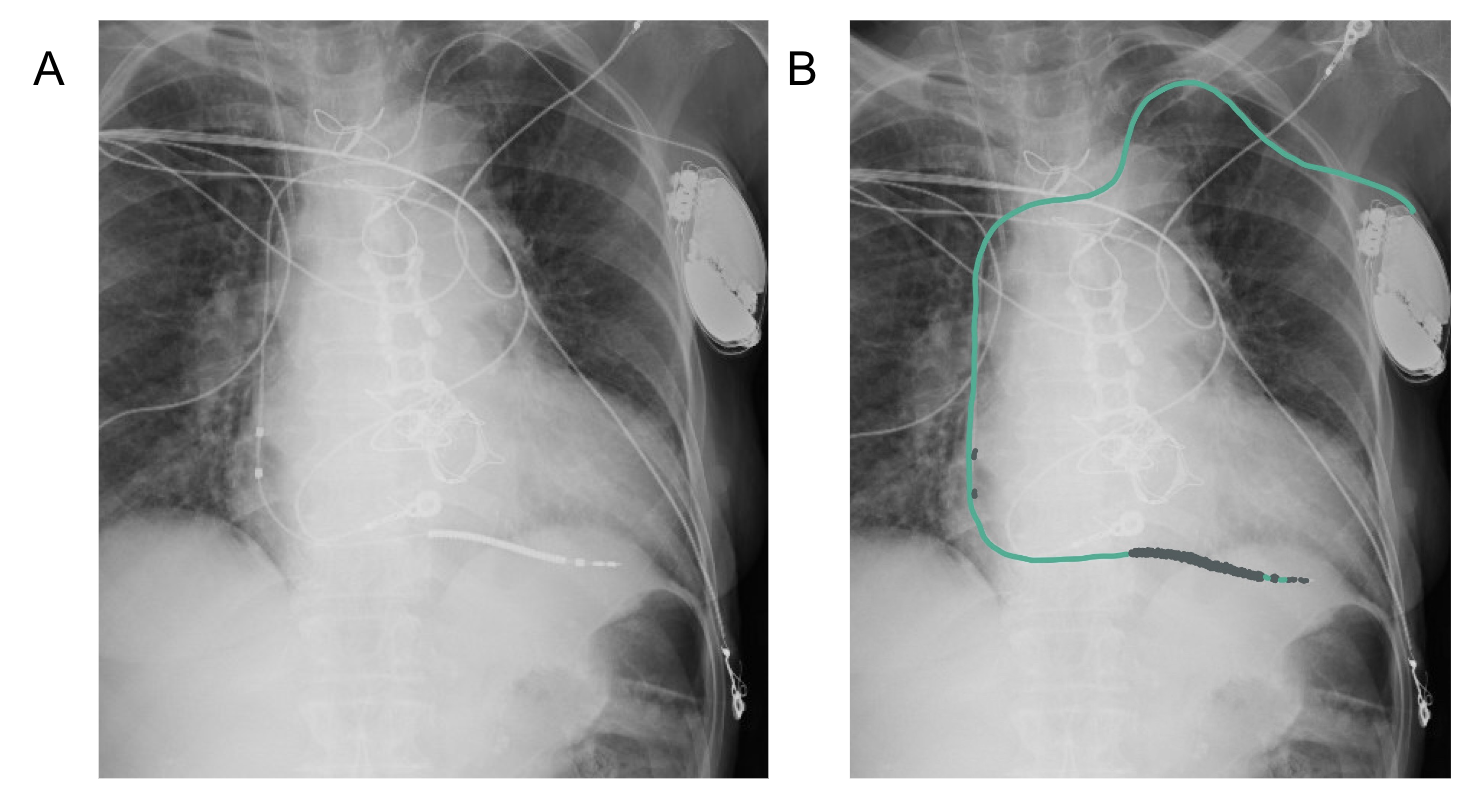

Figure 4A shows a patient with a single chamber defibrillator lead in the right ventricle, highlighted in green in 3B. Notice how this wire is thick (outlined in grey) unlike the thin pacemaker leads (seen in Figure 2) as the defibrillator requires this thicker coil to deliver a shock if needed.

The picture on the left shows a CXR of a patient with a CRT-D. The picture on the right shows the RA lead (pink), RV lead (green), and the blue lead (i.e. the lead that goes through the coronary sinus to stimulate the LV). Note the thick defibrillator wire, making this CRT and CRT-D. (rather than a CRT-P, pacemaker).